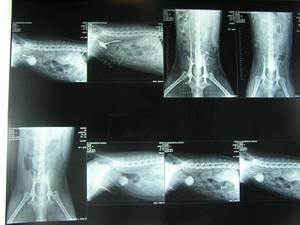

IMPRESIÓN DE LAS IMÁGENES: mediante la impresora láser DRY-VIEW, que está conectada en la network del hospital, imprimimos una o varias imágenes en el mismo soporte. |

SOPORTE:varias radiografías en el mismo soporte plástico |

ARCHIVO: ya no es necesario archivar las radiografías. Se guardan en el ordenador y se consultan e imprime n cuando sea necesario. |